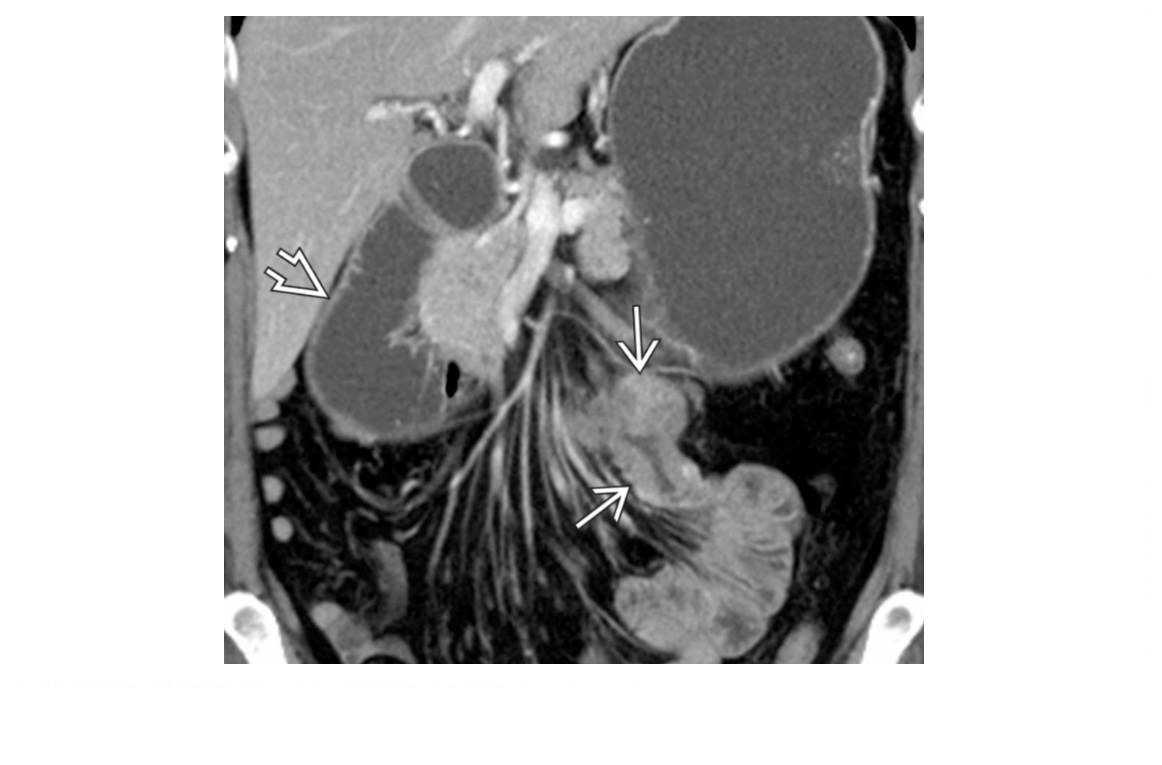

CT enterography features of active Crohn’s disease

**mucosal hyperenhancement **- most sensitive indicator but seen in other bowel diseases most specific sign for chrons - **Prominence of the vasa recta adjacent to the inflamed loop of bowel (comb sign) along with increased mesenteric fat attenuation** wall thickening (thickness >3 mm) CT enterography to depict extra-enteric disease/complications including -obstruction -sinus tract -fistula and abscess formation long-standing/inactive features include -submucosal fat deposition -pseudosacculation -surrounding fibro-fatty proliferation -fibrotic strictures MR enterography and enteroclysis - MR enteroclysis was superior to MR enterography in demonstrating mucosal abnormalities. -MR enteroclysis better bowel distension but not necessarily better diagnostics -MR enterography is more acceptable to the patient than MR enteroclysis